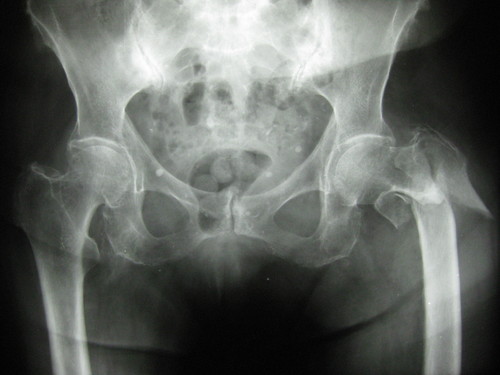

El diagnóstico de la enfermedad es fundamentalmente clínico y radiológico. La variabilidad interobservador al discernir grupos diferenciados de pacientes con gonartrosis sigue siendo un problema para poder realizar terapias y estudios que homogenicen las conclusiones. La escala radiológica de Kellgren y Lawrence (KL)2 sigue siendo en la práctica clínica habitual uno de los instrumentos más utilizados para establecer una gradación de la enfermedad (Figuras 1y 2). Además, la existencia de dolor o de incapacidad para actividades diarias como síntomas subjetivos o difícilmente medibles hace que se recurra a diversos cuestionarios funcionales, como el WOMAC (Western Ontario and McMaster Universities Osteoarthritis Index), que nos ayuden en la decisión terapéutica final, pero tampoco están exentos de cierto grado de variabilidad interobservador3. Esto, como veremos, es importante al establecer estudios y estrategias de tratamiento que resulten en evidencias sostenibles. La preocupación real del facultativo hoy en día es establecer una línea de corte entre la terapia conservadora eficaz, en la que incluimos fisioterapia, analgésicos como paracetamol,antiinflamatorios no esteroideos (AINE), inhibidores de la  ciclooxigenasa 2 o terapias intraarticulares como el ácido hialurónico y los corticosteroides intraarticulares, y la cirugía.

Figura 1. Gonartrosis de grado 0-1 KL

111

Figura 2 Gonartrosis de grado 3 KL

222